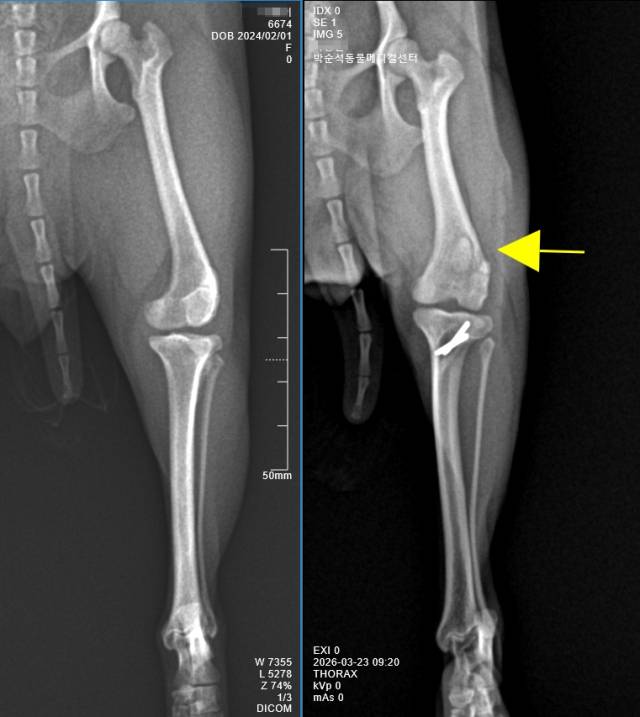

급속한 반려동물 문화의 확산과 더불어 국내 수의학의 위상 또한 눈에 띄게 높아지고 있다. 그 배경에는 한국만이 보이는 하나의 특징적인 의료 현상이 존재한다. 바로 세계 어느 나라보다 슬개골 탈구 수술의 빈도가 유난히 높다는 점이다.

국내 반려견은 소형견의 비중이 유난히 높다. 주거 환경의 특성상 작은 체구의 개를 선호하는 경향이 강해, 말티즈·포메라니안·푸들 등 주요 품종 역시 다른 나라에 비해 체구가 더 작은 경우가 많다. 이러한 특성으로 인해 슬개골 탈구와 같은 골격계 질환이 잠복되어 태어나는 개체들이 많아졌다.

그 결과, 세계 어느 나라보다 슬개골 탈구 수술의 빈도가 높으며, 수술의 난이도 또한 높은 편이다.

체중 3kg인 반려견의 슬개골탈구 수술 공간은 사람의 손가락 관절 정도에 비유될 정도다. 그 좁은 공간 내에서 활차구를 깍아내고, 경골결절을 자른 후 변위시켜 고정하는 섬세한 시술이 이루어진다. 이처럼 소형견을 대상으로 한 고도의 섬세한 시술들이 축적되면서, 국내 반려동물 수의학의 수준은 빠르게 발전해 왔다.

같은 '슬개골 탈구 수술'이라는 이름을 사용하더라도, 실제 적용되는 수술방법은 골의 변형정도, 골밀도 정도, 염증의 진행 여부 등을 고려하여 다양하게 적용되어 진다. 또한 수술 후 X-ray 검사에서 슬개골의 위치가 정상적으로 교정된 것으로 보이더라도, 임상적으로는 통증이 지속되는 경우가 적지 않다. 경우에 따라서는 퇴행성 관절염이 진행되며, 보행 장애와 만성 통증으로 인해 삶의 질이 저하되는 결과로 이어지기도 한다.

따라서 수술에 앞선 환자견의 정밀한 평가는 무엇보다 중요하다. 개체에 따라서는 수술 전 CT 검사가 필요한 경우도 적지 않다. 또한 골밀도가 충분하지 않은 경우에는 자가 골이식이 필요할 수 있으며, 슬개골 탈구로 내원했던 사례에서 실제로는 전방십자인대 손상이 동반된 경우도 빈번하게 확인된다.

그래서 슬개골 탈구 수술은 수술에 앞서 환자견에 대한 내과적 평가와 골밀도, 관절염, 십자인대 평가 등의 검사 과정을 거친다. 골변형 및 골질환이 염려된다면 CT 검사가 선행되기도 한다.